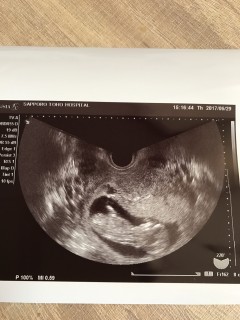

寝ていたようで動いてるのは見れませんでしたが、心臓はチカチカちゃんと動いていました! 手がイエイ!ってやってるみたいでした!笑 このまま順調にすくすく育ってね。

やっと12w。へその緒もしっかり確認して、手足をばたつかせてて可愛かったです(^^)